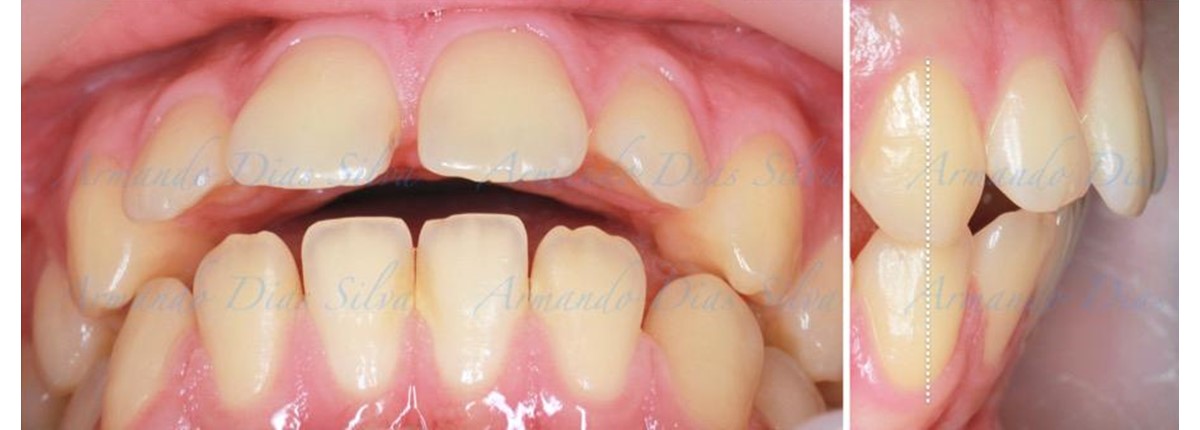

Principal queja del paciente: Protrusión del incisivo central y mordida abierta. El paciente rechaza la expansión del arco palatino (MARPE) y las extracciones.

Este paciente adolescente presenta molares de Clase II y no le gusta su mordida abierta ni lo protrusivos que son sus dientes frontales. Por sus fotografías faciales, parece que su mandíbula es retrognática o le falta volumen en la barbilla. El historial del paciente también indica que existe un problema funcional al no haber guía de los incisivos.

• Molares de clase II

• Diastema

• Espaciamiento leve de las arcadas superior e inferior (deficiencia transversal de 3,45 mm)

• El primer molar superior derecho está en una posición más mesial que el primer molar superior izquierdo

• Deficiencia transversal maxilar leve (3,45 mm)

• Incisivos superiores e inferiores proclinados

• Orientación canina desfavorable